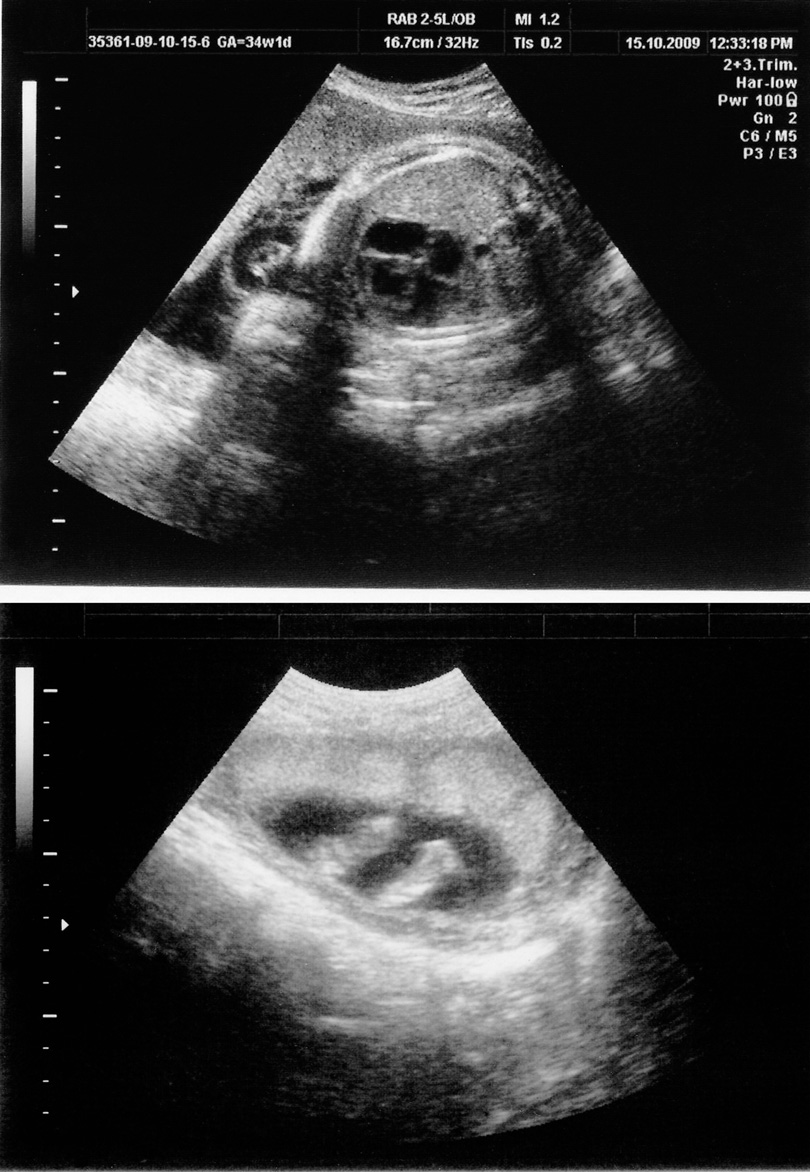

Obstetrical

Ultrasound